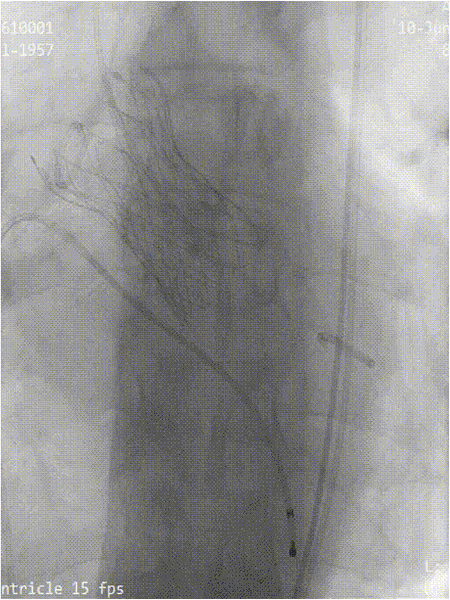

手术现场